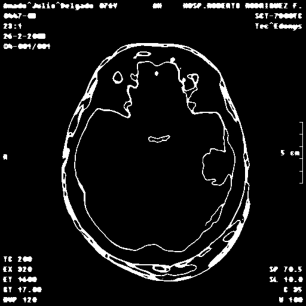

An example of an applications of our proposed strategy to a medical image is shown in Figure 7. In this case, we used different values of and in the . This is a preliminary result. A deeper paper about these results will be published.